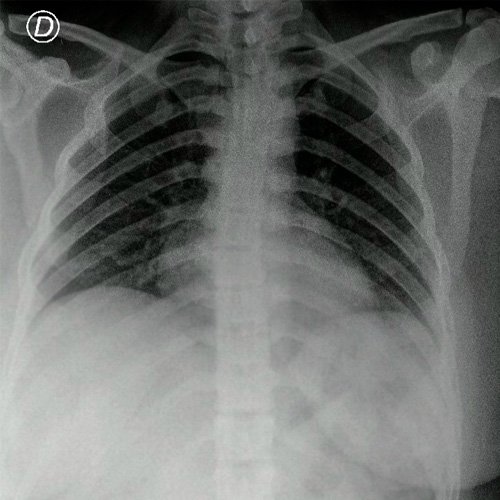

Anexo 1. Radiografía de tórax frente

• Radiografía tórax frente (Dia 0): centrada, bien inspirada y penetrada. Indice cardiotorácico conservado.No se observan infiltrados pleuroparenquimatosos. Senos costofrénicos y cardiofrénicos libres.